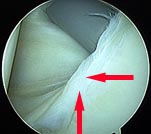

Arthroscopic Repair of Shoulder Dislocation